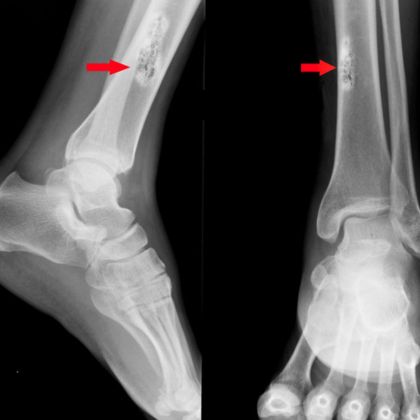

B. Badania obrazowe

- Rentgen: Rentgenografia jest często wykorzystywana jako pierwsze badanie obrazowe w diagnostyce nowotworów kości. Pozwala ona na uzyskanie obrazu struktury kostnej i potencjalnych zmian nowotworowych.

- Scyntygrafia kości: Badanie scyntygraficzne pozwala na wykrycie zmian nowotworowych w kościach, nawet przed pojawieniem się zmian na obrazach rentgenowskich.